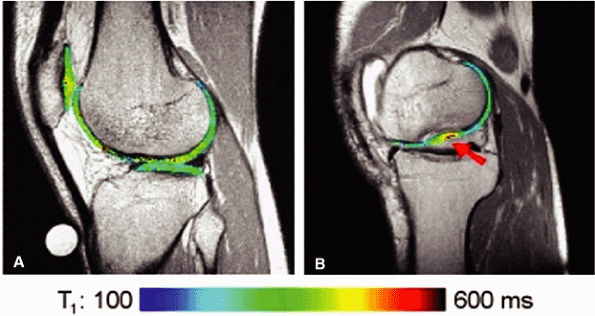

![]() |

|

FIGURE 1.18 ● Spin-echo, 8 echoes (10 to 80 msec). Note the signal attenuation in the patellar cartilage. This type of sequence is used to produce cartilage T2 color maps.

FIGURE 1.19 ● Color map (A) showing T2 values from 20 msec in red to 75 msec in blue, with calculated T2 values from the region of interest (ROI). ROI #1 green curve (B) shows the 8-echo signal pattern, and the red curve shows the calculated monoexponential fit.

FIGURE 1.20 ● Clinical examples of T2 mapping at 3 T. Color map showing T2 values from 25 msec in red to 75 msec in blue. (A, B) Osteoarthritis (arrow) is not visible on the conventional T2 image (A). (C, D) Autologous osteochondral implant (mosaicplasty) of the medial femoral condyle with mild prolongation of T2 values. (Courtesy H.G. Potter, HSS, NY)

FIGURE 1.21 ● dGEMRIC T1 maps at 1 T. (A) Asymptomatic volunteer (in-plane resolution 450 μ × 450 μ). (B) Patient post-autologous chondrocyte transplantation (in-plane resolution 570 μ × 570 μ). The graft is indicated with an arrow.